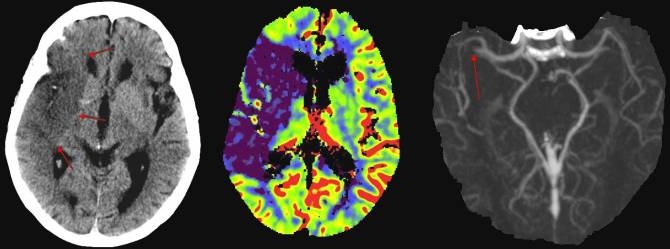

A su vez, los investigadores del CIC biomaGUNE (Abraham Martín y Jordi Llop), mediante técnicas de imagen cerebral funcional como el PET (del inglés, Positron Emission Tomography) han observado que los niveles de xCT están elevados en ratas sometidas a isquemia, lo cual subraya su importancia en el proceso de Ictus.